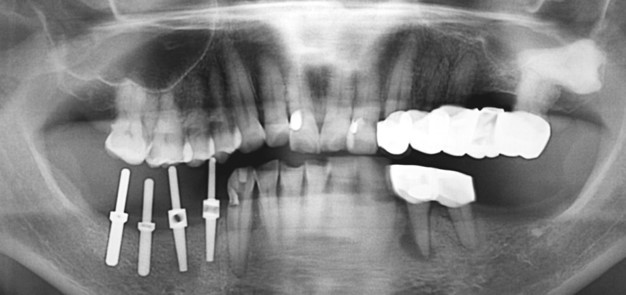

Submerged implantÀÇ ´ÜÁ¡

Wide fixture(Á÷°æ 5.5mm)

Sub typeÀº ÇȽºÃÄ Á÷°æ°ú´Â º° °³·Î ¾î¹þÀº ¸ðµÎ µ¿ÀÏÇÑ »çÀÌÁî´Ù. Ư¡ÀÌÀÚ ÀåÁ¡ÀÌ´Ù. ÇȽºÃİ¡ ºÎ·¯ÁöÁö ¾Ê¾Æ¼ ´ÙÇàÀÌ´Ù. ±×·¯³ª ¾î¹þÀÇ ¹Øµ¿ÀÌ ºÎ·¯Áø °Íµµ ¸Å¿ì Å« ÇÕº´ÁõÀÌ´Ù. ºÎ·¯Áø ¹Øµ¿À» ±ú²ýÇÏ°Ô »©³»´Â °Íµµ »ó´çÈ÷ Èûµç ÀÏÀÌ´Ù.